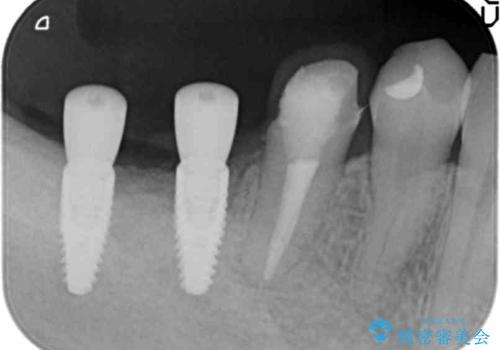

インプラント治療による咬合機能回復

- 失ってしまった奥歯の咬合機能の回復を求めて来院されました。

骨の幅が十分にないのでインプラント治療に伴い、人工骨の造成を同時に計画します。

インプラントは高い確率で骨に結合し、しっかりとした咬合力を回復することができます。

長年安心してしっかりと噛んでいただけるよう今回は骨を増成する治療計画としました。